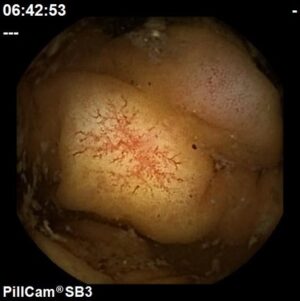

Úlcera com vaso visível intestino delgado

Hospital Senhora da Oliveira (Guimarães)